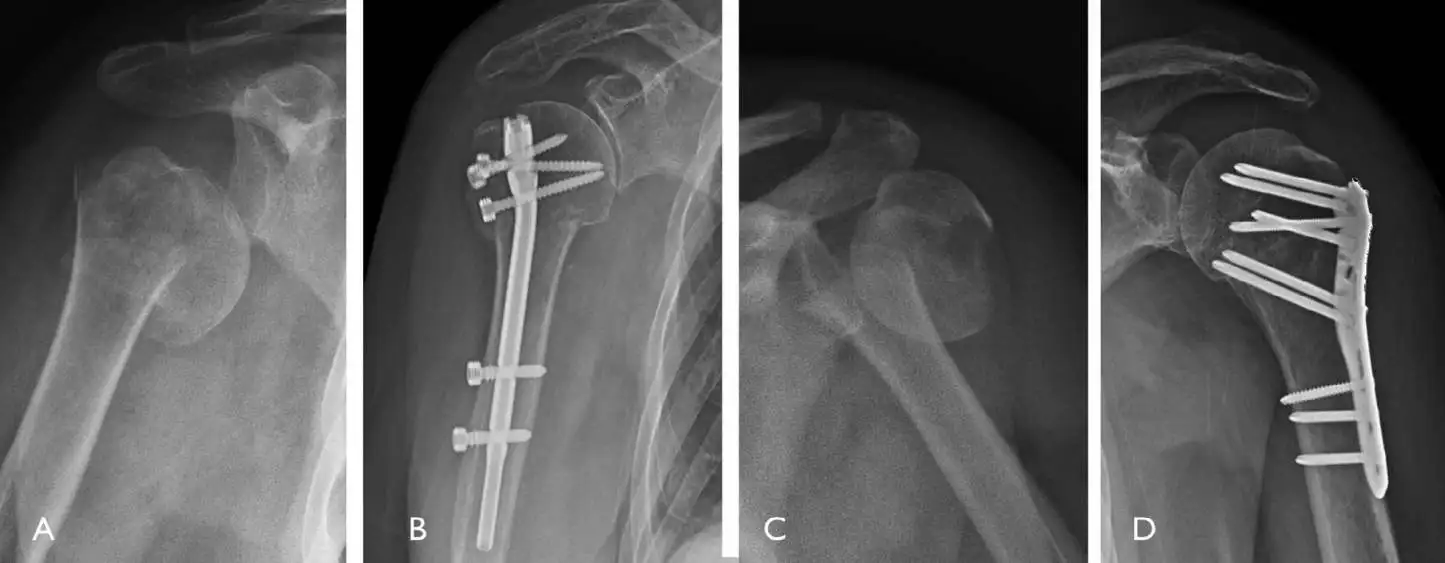

Product Features of VA Variable Angle Distal Lateral Humeral Locking Plate

◆ Design of distal multi-axial locking hole

The maximum angle of the multi-axial locking screw in all directions away from the axis is 15 °, which can better support the joint surface and fix the fracture block, enhance the anti rotation stability by cross fixation of the fracture block, and provide the possibility of re implantation of the screw.

◆ Anatomical Design

Even Complex fractures can be perfectly fitted without shaping.

◆ Stable Angulation

The angular stabilization structure is designed to improve the holding power of osteoporosis patients and multiple fracture cases.

It provides the best stability and helps to prevent reduction loss.

◆ Round Blunt Head Design

Reduce the impact of shoulder seam and prevent postoperative pain.

◆ Locking & Complression Design

To meet the doctor's requirements for different fractures, compression and locking functions can be flexibly selected in one hole.

Fixations at different angles is selected according to different fracture sites to form different angle structures so as to

achieve the stability of later reduction.

◆ Head End

Locking holes are the main part of the head, which are designed from different angles. The screw is allowed to be stably placed in the axial direction, so that the structure is stable and the elongated type can cover a wider range of fractures.

◆ Main Part

Conjugative hole for locking & compression. Free choice of locking screw & compression screw.